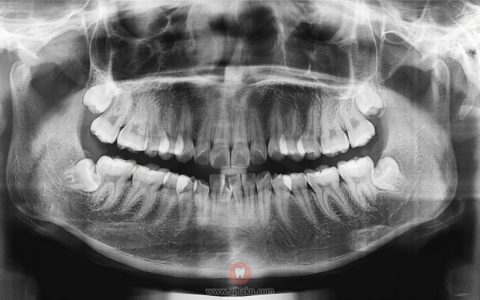

牙齿是由牙冠和牙根组成的,牙冠就是我们看到的口腔部分,而牙根埋在颌骨里。

上图的白色影像就是牙齿在牙片上的显示

牙片就是牙齿的X光片,又叫口内标准片,是一个常见的辅助检查手段。

它就像医生的透视眼,能透过外表看到内部结构,这对于医生准确诊断及治疗,有着非常大的作用。